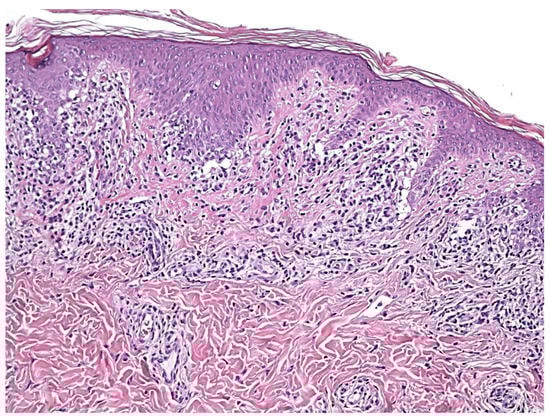

4. Histopathology